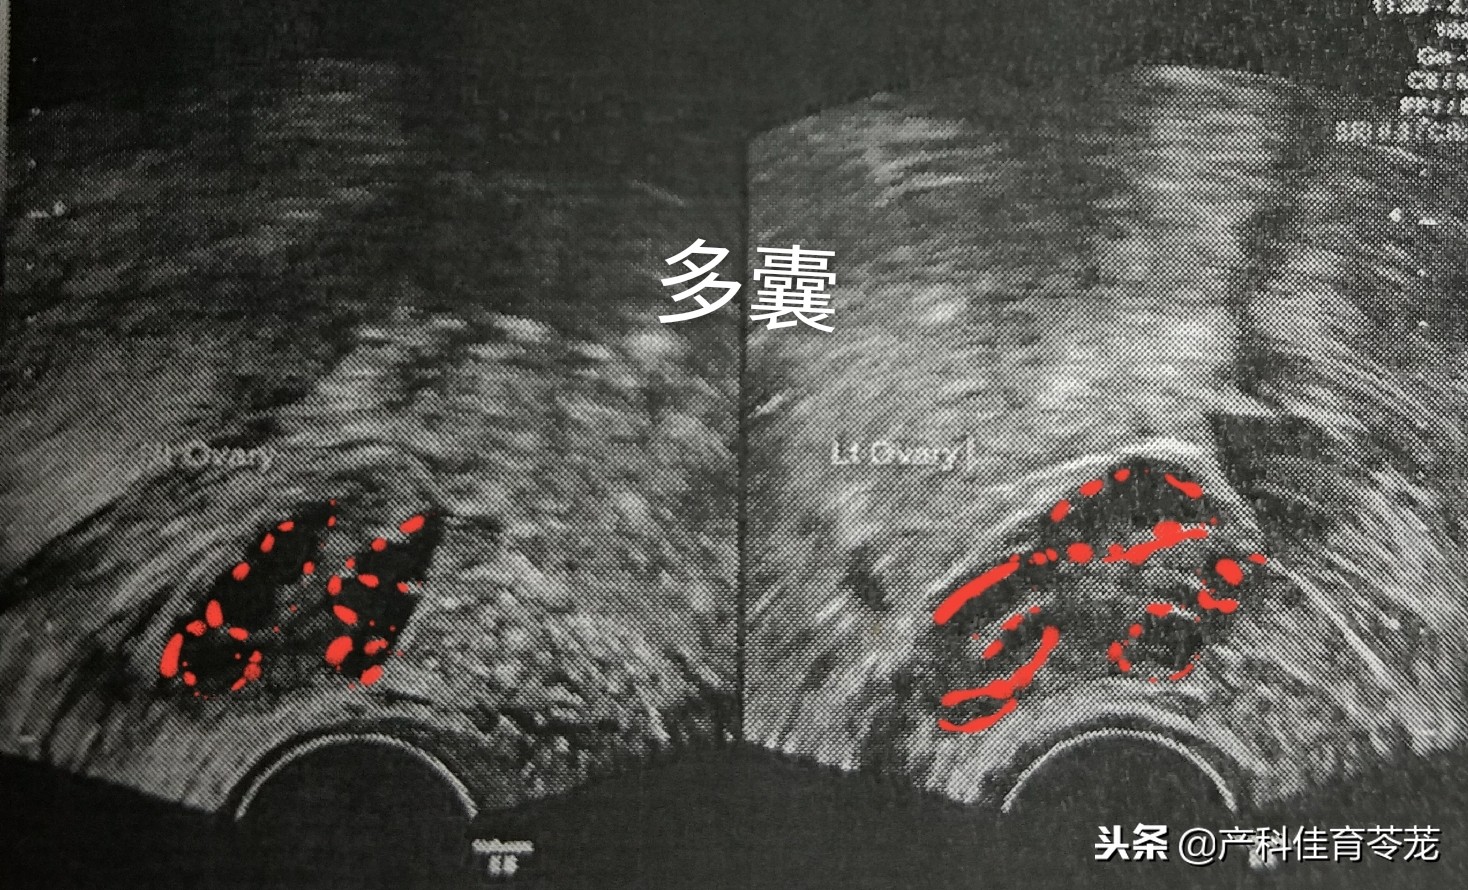

2、多囊卵巢

同样是卵巢增大,但B超图像是这样的:

可以看到卵巢内有很多个黑色的区域,专业术语称为“液性暗区”,其实是多了卵泡。

多囊卵巢属于内分泌紊乱,多数患者有闭经或者月经稀发(很长时间才来一次月经)、多毛、*疮痤**等雄激素增高的表现。